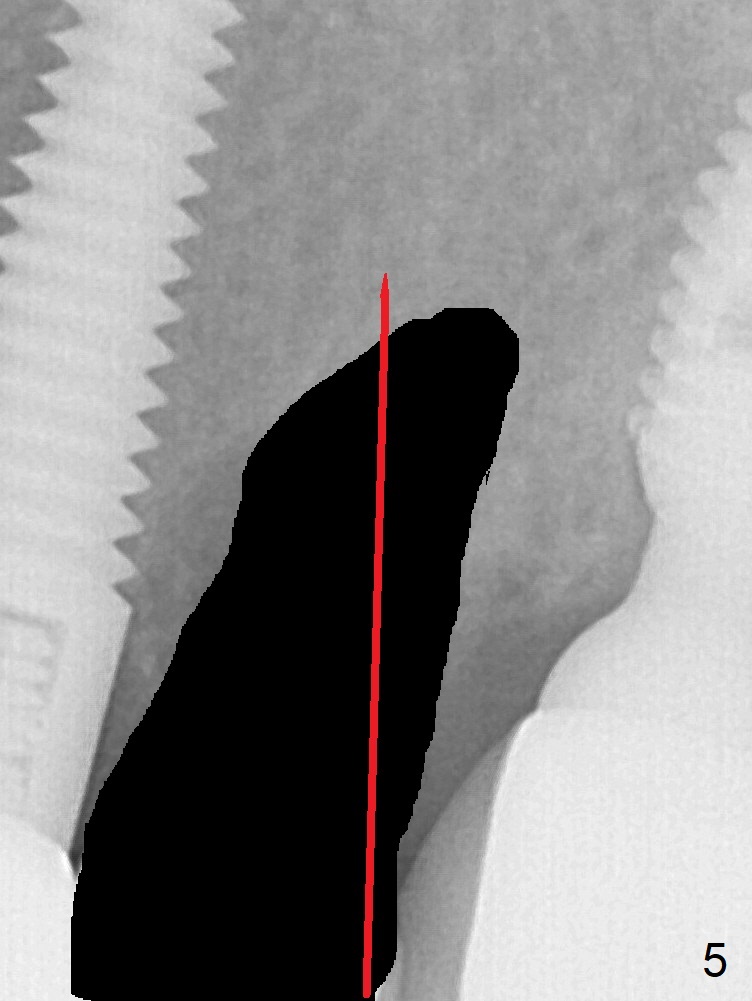

A 59-year-old woman has mild discomfort in the upper left quadrant, which is alleviated by salt water rinse. The buccal gingiva recedes at #13 with mesiobuccal swelling and deep pocket (Fig.1,3), corresponding to the mesial radiolucency (Fig.2 *). The tooth appears to have vertical fractured root, as related to the retention post. Since the root tip curves distal, the initial osteotomy (Fig.5 red) should be established in the mesioapical slope after extraction (black). Following initial entrance, the trajectory will be changed to the long axis of the space (Fig.6) with PA to be taken. Measure the depth of the buccal crest against the buccal, proximal and palatal gingival margins. Place an implant, the same as #12 (4.5x20 mm) unless the mesiobuccal defect is extremely large (UF).